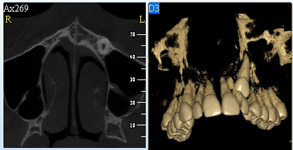

3D DVT - NewTom

Je speciální zubní digitální tříprostorový tomograf (3D), který umožňuje na základě jediného snímkování vytvořit všechny typy RTG zobrazení, které jsou pro lékaře potřebné. Díky používané technologii tzv. „kuželového paprsku“ a speciálním senzorům je výrazně zmenšená dávka záření - o více jak 80% proti klasickému CT vyšetření. To je významné zejména u dětí. Pomocí tohoto přístroje je možné zjisti skutečnou situaci v čelistních kostech pacienta tedy množství kosti - můžeme změřit skutečnou šířku i výšku kosti, i kvalitu kosti (hustotu) v místě uvažované implantace. 3D (tříprostorové) zobrazení umožňuje zvýšit prostorovou představu operatéra ještě před vlastní operací a zároveň pacientovi lépe objasnit a ukázat oblast plánovaného zavedení implantátu.

Pacient „neumí číst“ RTG snímky, ale díky 3D zobrazení vidí „svoji skutečnou čelist“ - např. jak je nízká či úzká, vidí průběh nervu nebo velikost čelistní dutiny, což mu umožní i pochopení nutnosti v některých případech provést pomocné zákroky ještě před vlastním zavedením implantátu (viz. kostní štěp, sinus lift, kostní granulát...).

Vyšetření pomocí tohoto přístroje používáme i ve stomatochirurgii (zlomeniny čelistí, zuby moudrosti, cysty, onemocnění čelistního kloubu), ortodoncii (retinované zuby, nadpočetné zuby), parodontologii atd.